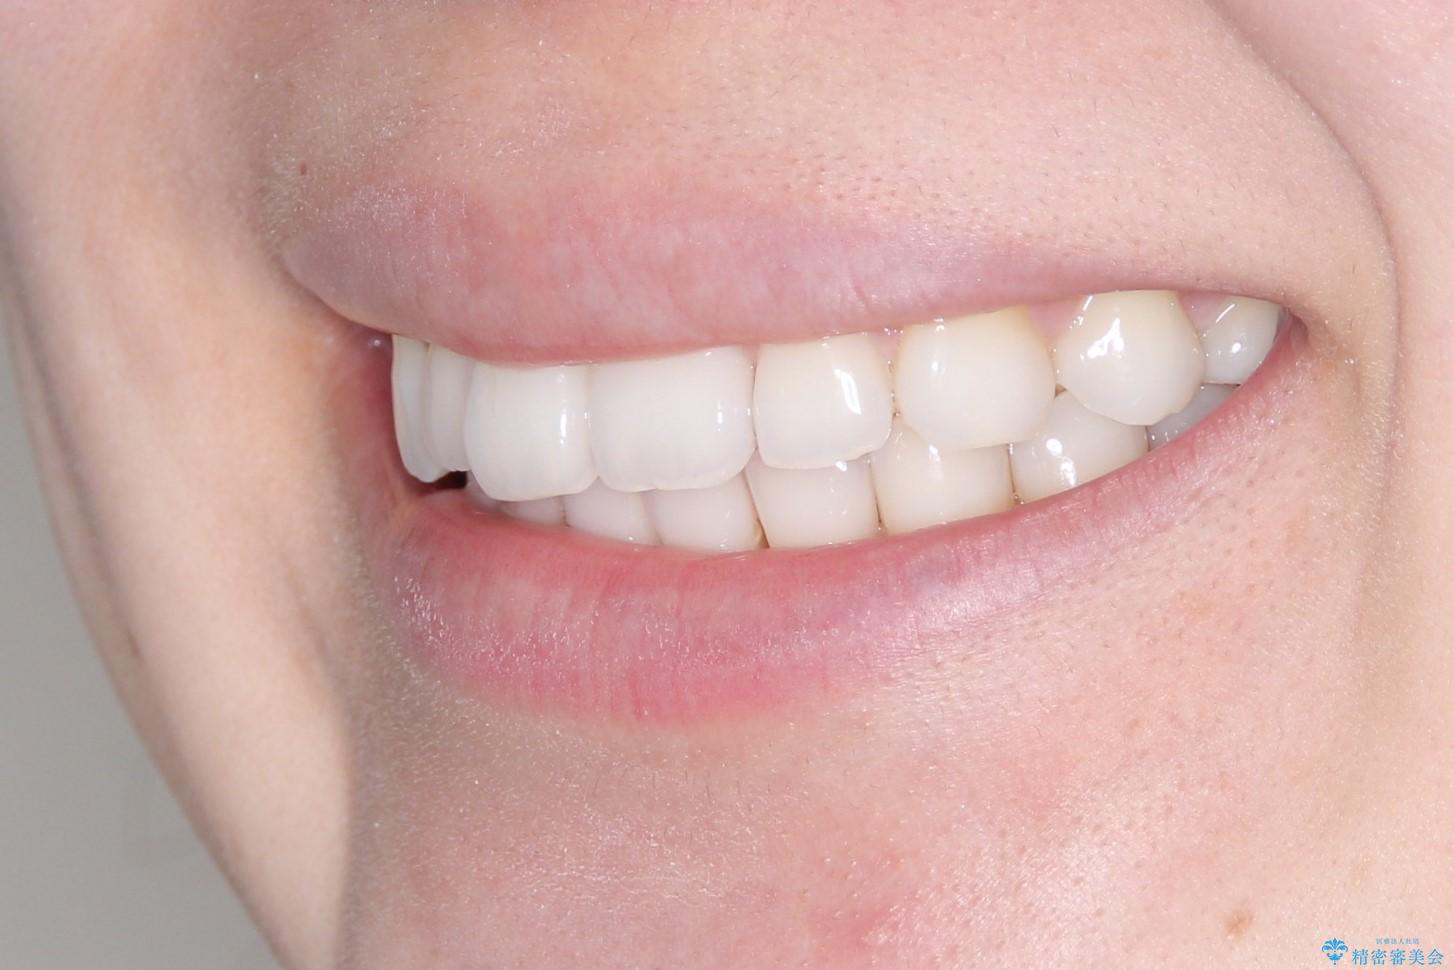

インビザラインで出っ歯を改善する 抜歯をしないinvisalign治療

- 非抜歯・遠心移動による前突の改善をマウスピースにて計画した。

非抜歯矯正の場合、大きく前歯を下げることはできませんが、奥歯の遠心移動や歯のサイズダウンにより歯軸を立て、見かけ上の出っ歯感をある程度改善することができます。